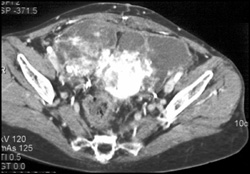

Uterine Abscess